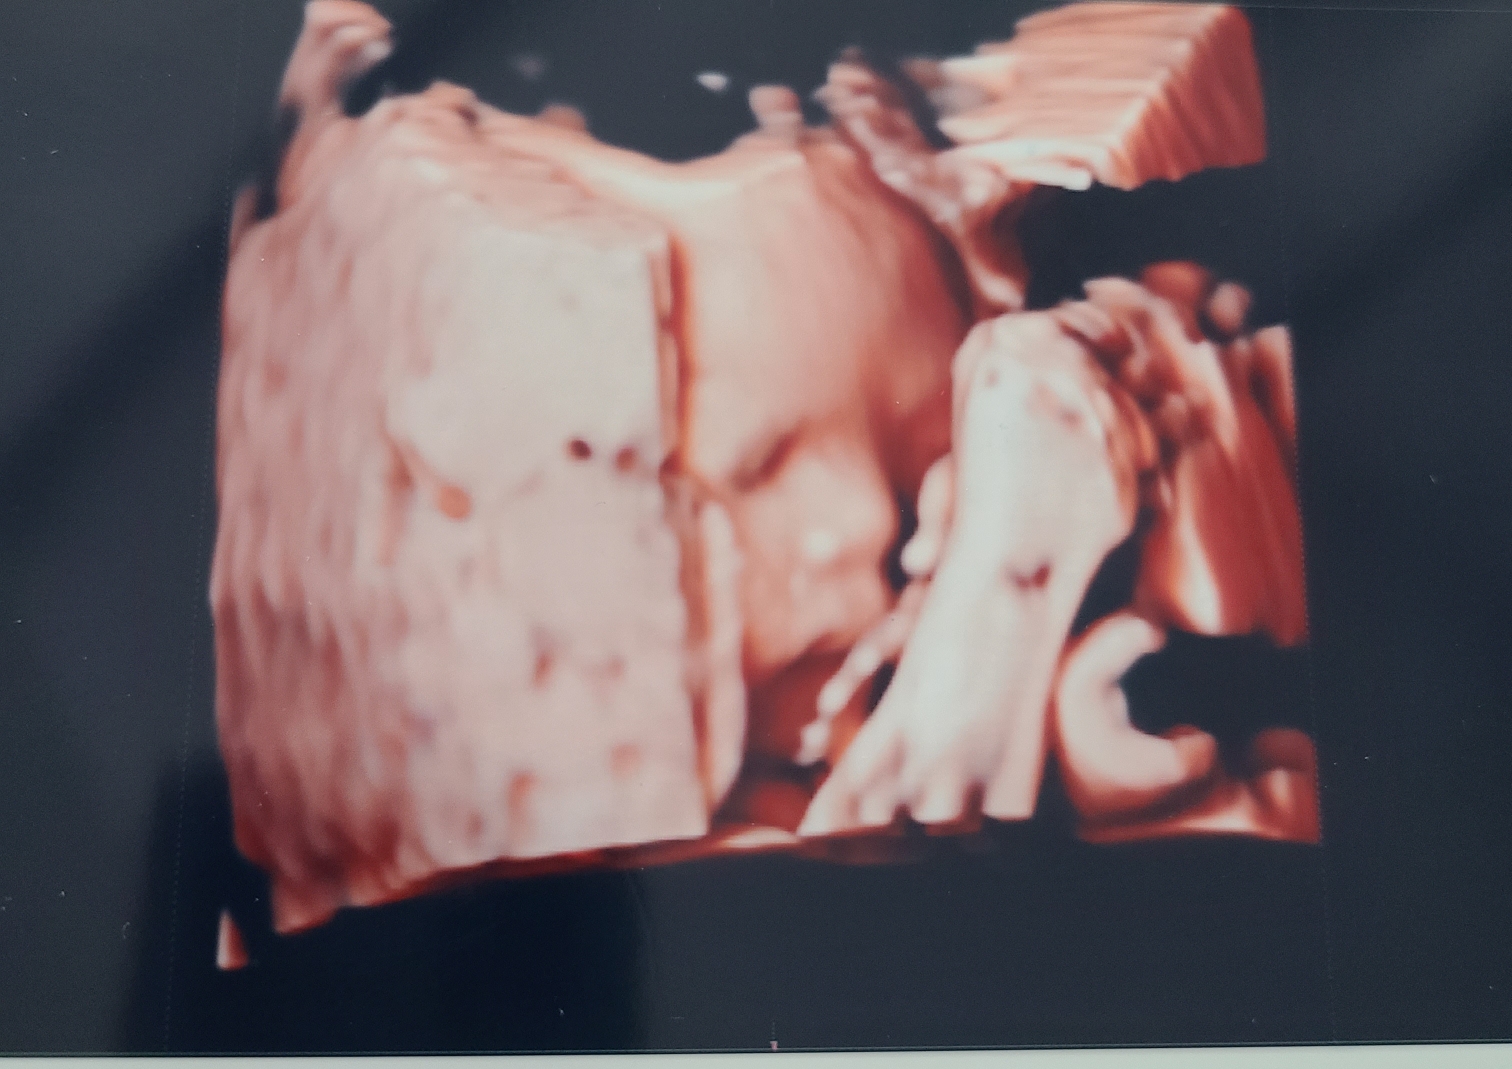

3일 후 초음파 보기는?

나름 성공적이었답니다.